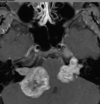

Qual o padrão da imagem na AMS-C?

Atrofia de cerebelo (vermis) e tronco (principalmente ponte); Hipersinal T2 na ponte: Sinal da cruz na ponte (não patognomônico), perda da barriguinha da ponte, Hipersinal nos pedúnculos cerebelares médios;